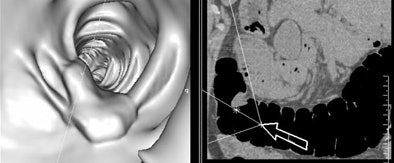

![]() |

| Colorectal polyp seen in 3D endoluminal view (left) and 2D axial view (right). Images courtesy of Dr. Andrik Aschoff. |